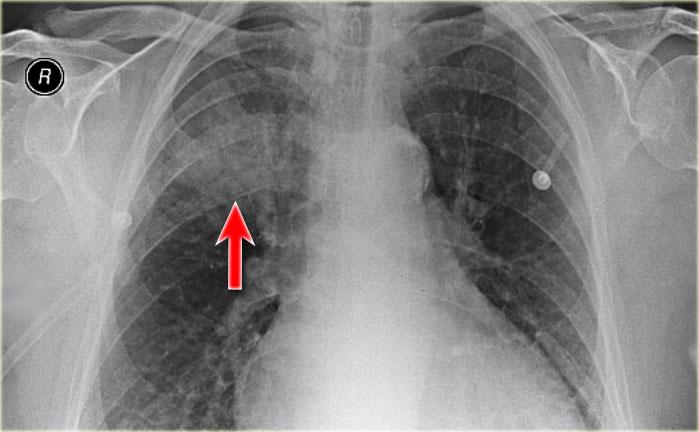

Viêm phổi thùy

Trên X-quang ngực có vùng tăng tỷ trọng bờ không rõ ở thùy trên phổi phải mà không có mất thể tích.

Rốn phổi phải ở vị trí bình thường.

Lưu ý dấu hiệu khí phế quản đồ (mũi tên).

Trong bối cảnh lâm sàng phù hợp, đây rất có thể là viêm phổi thùy hoặc phân thùy.

Tuy nhiên, nếu bệnh nhân này có sụt cân hoặc triệu chứng kéo dài, chúng ta cần đưa vào danh sách các nguyên nhân gây đông đặc mạn tính.

Đây là trường hợp viêm phổi thùy cấp tính do Streptococcus pneumoniae.